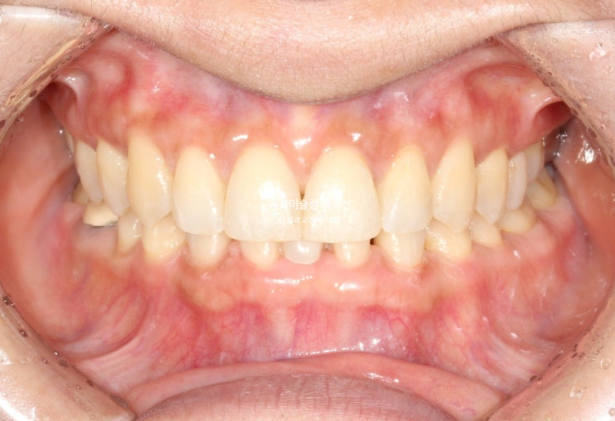

메릴랜드 브릿지가 들어간 후 어태치먼트를 전부 제거하고 치료를 마무리 하였습니다.

선천적 결손으로 벌어져 있던 빈공간은 깔끔히 해결이 되었습니다.

총 치료기간은 1년, 재제작은 1회 했고 교정치료 내원간격은 5개월 입니다.

24.08~25.08

쓰러져 있던 두번째 큰어금니는 잘 세웠습니다.